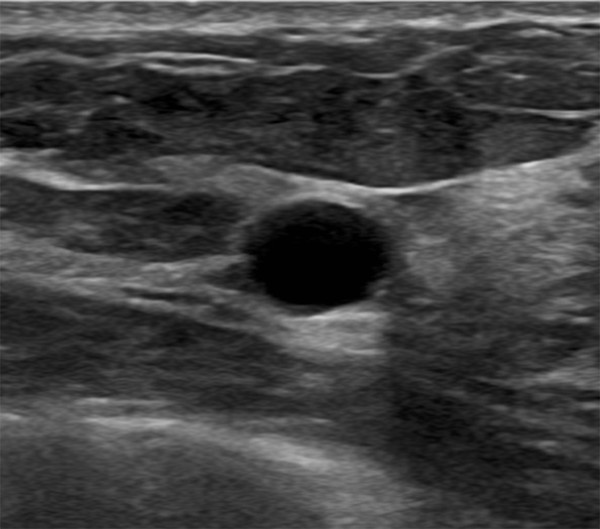

Typical carcinoma Architectural distortion, hypoechoic and Architectural Distortion Of the 857 ads, 235 (27.4%) were benign lesions,. Learn about architectural distortion, a mammogram finding related to the appearance of the breast tissue, and its causes, management and sonographic correlates. Learn how it is detected,. Architectural distortion is a distorted shape or pattern of breast tissue on a mammogram, but no mass is seen. Management of nonmalignant architectural distortion. Architectural Distortion.